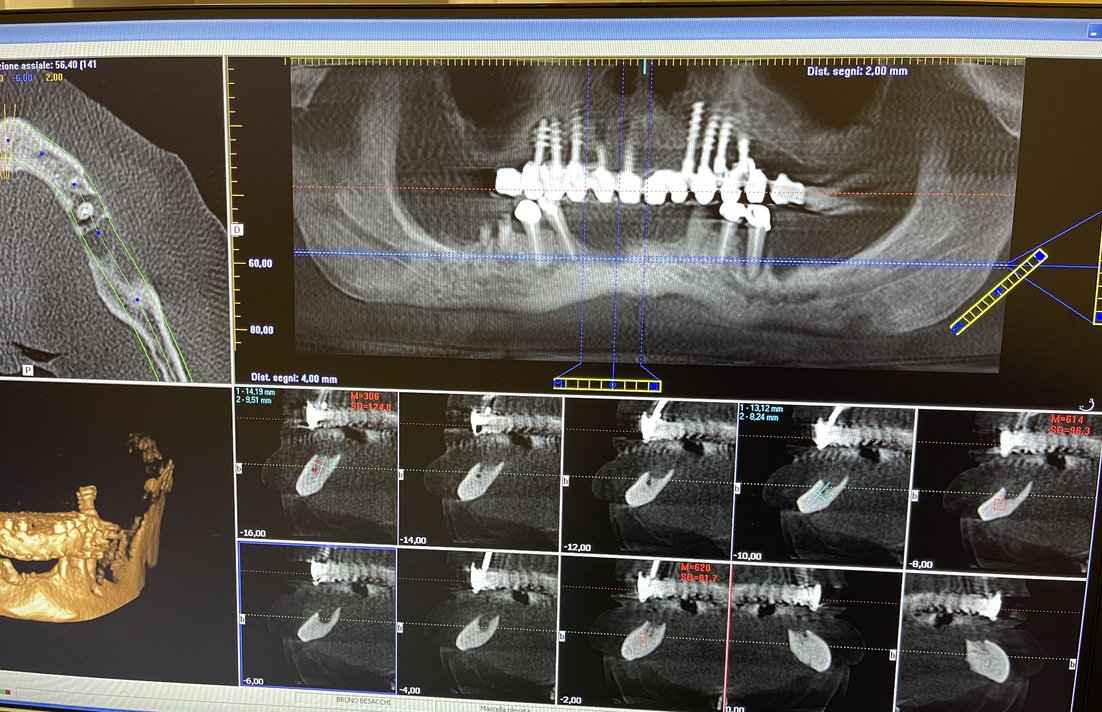

CASO CLINICO : Riabilitazione del 28/04/2021

In particolare considero notevoli i seguenti aspetti:

• 1 età del paziente. 83 anni

• 2 esecuzione dei primi 6 impianti: 25 anni fa

• 3 esecuzione dei 5 impianti successivi: 14 anni fa

• 4 medicinali assunti dal paziente: nessuno

• 5 presenza di impianti in zona tuber/pterigoidea

• 6 presenza di impianti inclinati di antica data

• 7 presenza di impianto piegato in 25. (Per parallelizzarlo)

• 8 presenza di due miniimpianti in 11-12

• 9 presenza di barra saldata nel settore superiore

• 10 grave parodontopatia del settore inferiore

• 11 problematiche igieniche

• 12 insuccesso implantare di impianto di Tramonte inferiore, impianto precedente al 2004, nel quadro della generale parodontopatia

• 13 l’inserimento dei tre impianti non ha comportato innesti di osso o di tessuti connettivali.

• 14 Non ha reso necessari scollamenti

• 15 Non è stata necessario isolare le emergenze dei nervi alveolari inferiori

• 16 Trattandosi di osso ad elevata densità si è ricorsi alla fresa elicoidale, strumento raramente utilizzato da noi perchè non necessario e perchè ci sono zone in cui il suo utilizzo comporta rischi chirurgici per noi non accettabili. Inoltre questa fresa asporta quantità discrete di osso che preferiamo resti dove la natura lo ha messo. Interessante il fatto che il diametro della fresa è di solo 2 mm

• 17 Trattandosi di osso denso, gli impianti utilizzati avevano un diametro di soli 4 mm dopo maschiatura col corrispondente maschiatore.

• 18 Al controllo del 3/5/2021 il paziente non è gonfio e riferisce che mangia finalmente bene.

• 19 Inizio intervento implantare alle 8.45. fine intervento implantare alle 9.36.

• 20 Cementazione del provvisorio, confezionato al momento, ultimata alle 10.30. durata totale permanenza del paziente in ambulatorio1,45 ore.

Le immagini forniscono nelle didascalie ulteriori informazioni.